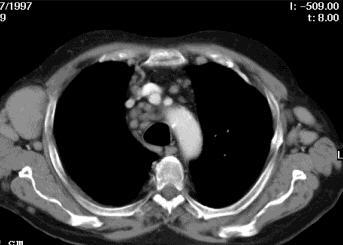

Perikarderguss

Akut auftretende perikardiale Flüssigkeitsansammlungen können ab ca. 250 ml zu einer Herzbeuteltamponade führen. Als Ursachen dafür kommen beispielsweise Aortendissektionen, perforierende Traumen, Urämie sowie bakterielle, virale und rheumatoide Perikardentzündungen in Frage. Computertomographisch lässt sich ein zirkulärer, dem subepikardialen Fettgewebe anliegender hypodenser Saum darstellen. Bei einer zugrunde liegenden Perikarditis können verdickte, kontrastmittelaufnehmende Perikardblätter nachweisbar sein.